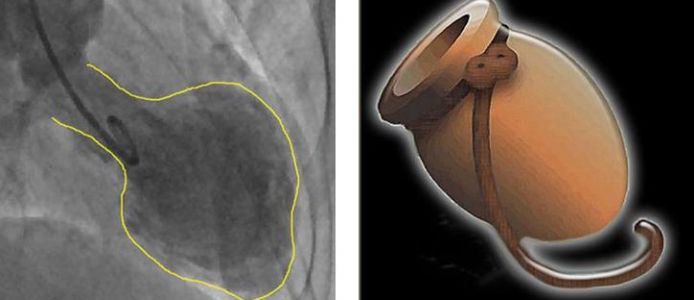

A new study reveals that the "broken heart syndrome" or also referred to as takotsubo syndrome may have longer-lasting damaging effects on the heart. Until now, it was thought the heart fully recovered from the syndrome, but new research suggests the muscle actually suffers long-term damage.

In the U.K., about 3,000 people suffer from this syndrome each year. It mostly affects women than men. The broken heart syndrome is caused by severe emotional distress such as the death of a loved one or bereavement. It is thought that this syndrome could cause temporary heart failure. Until now, it was thought the heart fully recovered from the syndrome, but new research suggests the muscle actually suffers long-term damage.

The study involved 52 people diagnosed with takotsubo syndrome. The researchers have examined them over the course of four months. They looked at how their hearts were functioning by using ultrasound and cardiac MRI scans. The results suggest that the condition permanently altered the pumping motion of the heart, delaying the twisting by the heart during a heartbeat.

They also found that the heart's squeezing motion was also reduced. Meanwhile, some parts of the heart muscle suffered scarring that had an impact on the elasticity of the heart, which inhibited the heart from contracting properly.